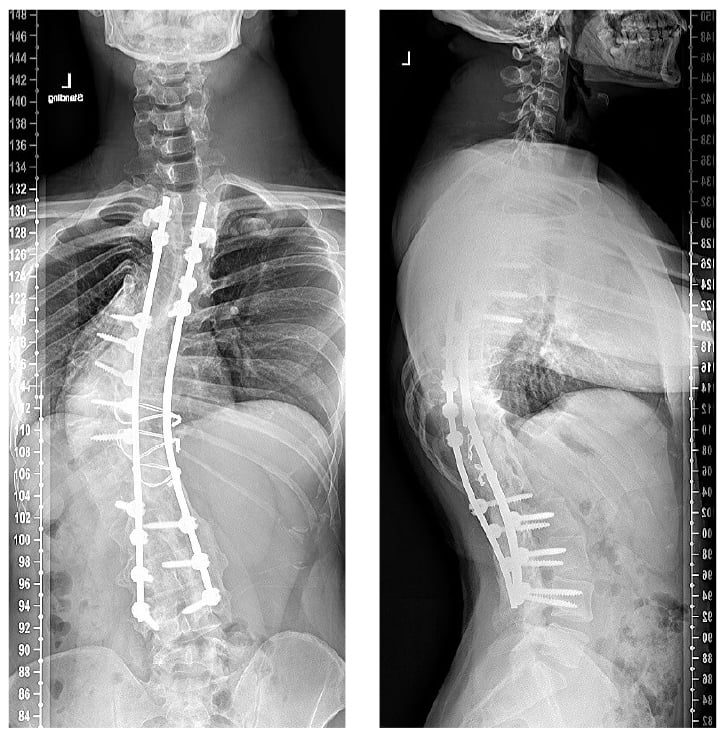

Postoperatively, the patient was hospitalized for 7 days and remained neurologically intact. He developed ileus that rapidly resolved after placement of a nasogastric tube; he mentioned discomfort in the rectus and anterior oblique muscles that resolved within 2 weeks and mild-to-moderate neuropathic pain in the legs that resolved by the 6-week follow-up. At 4-year follow-up, he maintained more than 50% correction to a 60° thoracic Cobb angle and a 25° thoracic kyphosis (Fig. 3). He gained nearly 6” in height and is now 5’9” tall.

Figure 3: At 4-year follow-up after T2–L4 posterior segmental instrumented fusion, the patient showed a greater than 50% correction to a 60° thoracic Cobb angle and a 25° thoracic kyphosis.